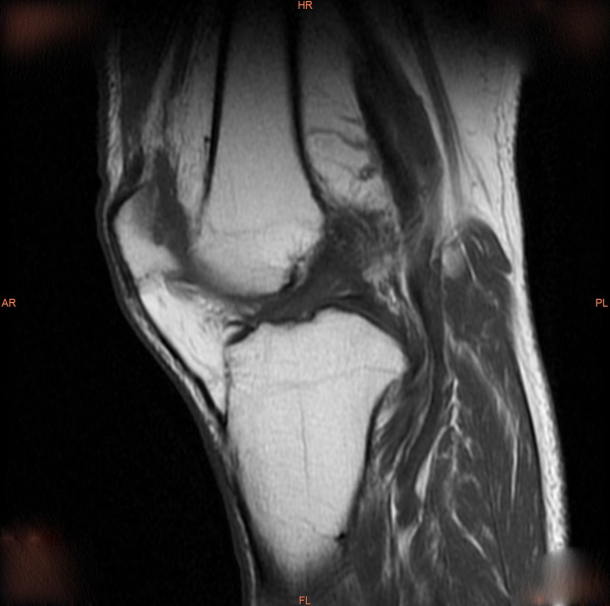

術(shù)前膝關(guān)節(jié)磁共振影像。

一個月前,80歲的黃爺爺(化名)漸感左膝關(guān)節(jié)不適,在一次日常的上下樓梯后,癥狀突然加劇,出現(xiàn)左側(cè)膝關(guān)節(jié)腫脹、疼痛,來到潛江市中心醫(yī)院骨外科Ⅱ住院治療。經(jīng)過詳細檢查后,黃爺爺被確診為“重度骨性關(guān)節(jié)炎伴膝內(nèi)翻畸形”。骨外科Ⅱ醫(yī)療團隊考慮到患者年齡較大且關(guān)節(jié)病變嚴重,在與家屬進行了充分溝通和全面評估后,最終決定采用全膝關(guān)節(jié)置換術(shù)進行治療。